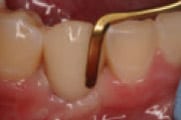

Figure 4

Trim Protemp™ Crown Temporization Material to obtain proper

height.